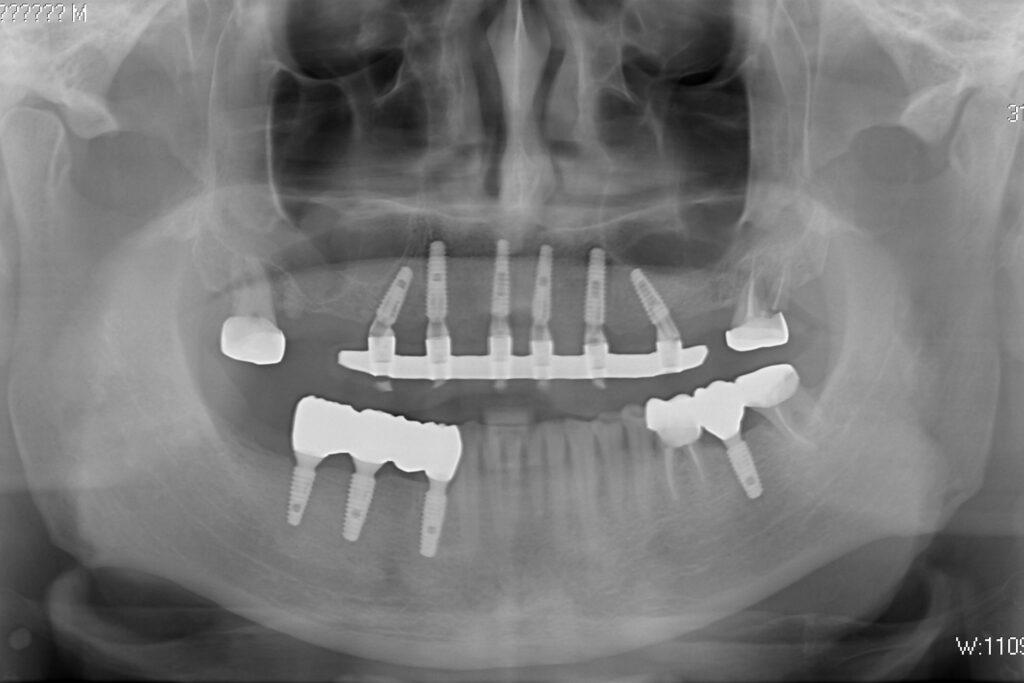

На консультации было принято решение о перепротезировании протезом из диоксида циркония на титановой балке.

Спустя 27 дней был зафиксирован протез с опопрой на дентальные имплантаты из диоксида циркония с каркасом из титана.

Пациенту были установлены 6 имплантатов Megagen AnyOne по системе All-on-6 на верхней челюсти и 4 имплантата на нижней по классической двухэтапной методике.